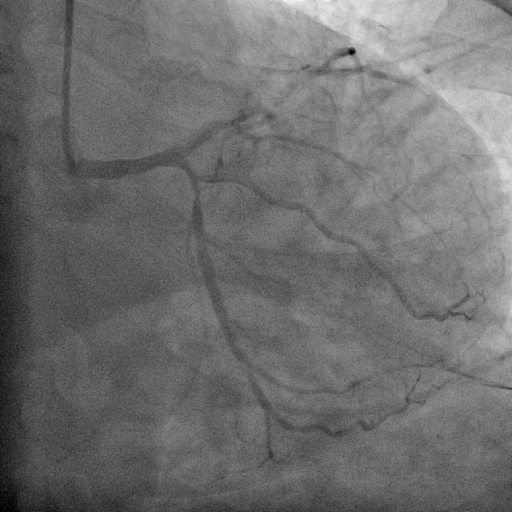

We decided to proceed with the primary percutaneous coronary angioplasty via right radial access by using the 5F JR 3.5 guiding catheter . We used Run through NS floppy wire for crossing culprit lesion to distal RCA but TIMI flow 0. We used micross 1.0 balloon for just cross the lesion and tracking balloon over the lesion . Then distal segment properly seen. Pre dilatation not done due to acute lesion and high chance of thrombus dislodgement and distal embolization . Direct stent 3.50 x 42 mm was implanted in proximal RCA to Mid RCA at 14 atmosphere pressure. Stent was well apposed and final result angiography was excellent and TIMI III flow without residual lesion and no distal embolization. the procedure done without any complications. Total Inj. heparin 10000 unit given and ACT was 298 sec.

SHAHIDUL ISLAM_(S8_F1-57).avi

SHAHIDUL ISLAM_(S12_F1-23).avi

SHAHIDUL ISLAM_(S14_F1-46).avi